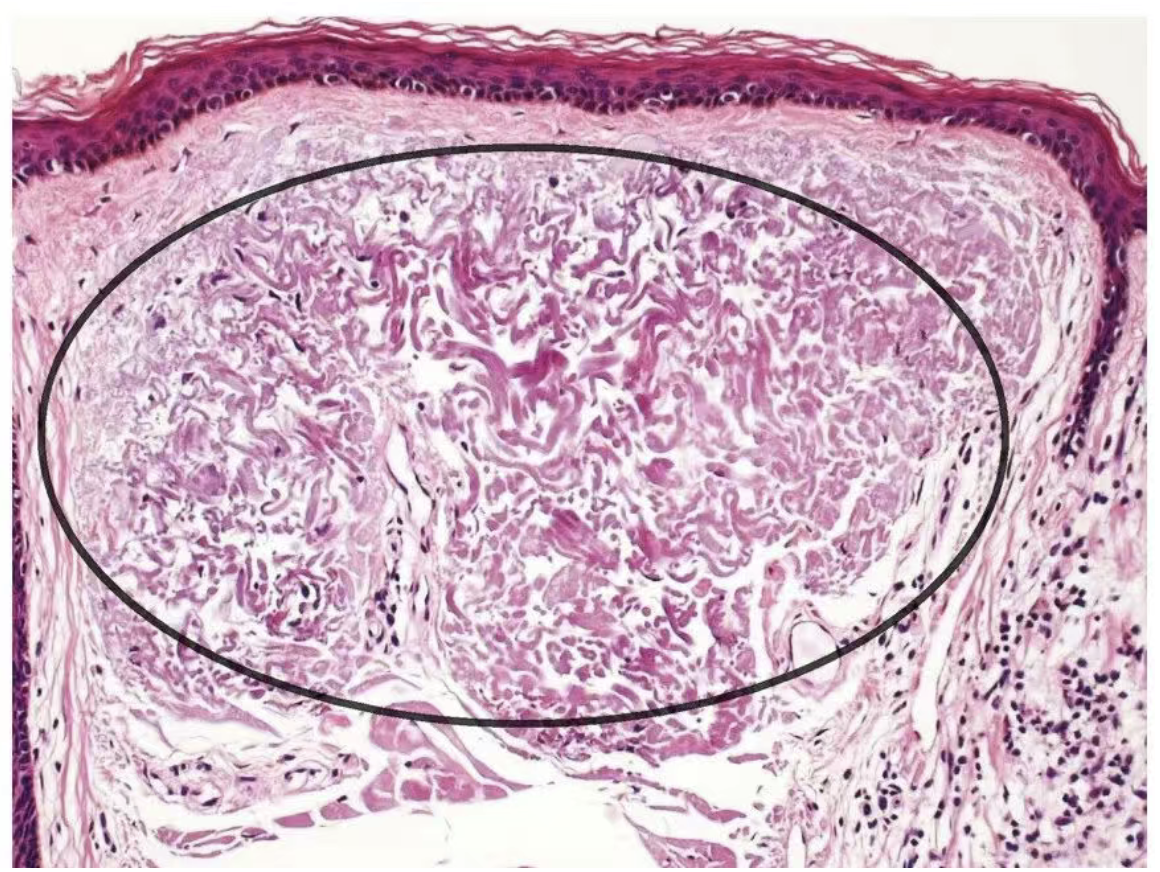

紫外线损伤后的胶原纤维:经过反复紫外线暴露,胶原纤维变得卷曲、破碎、杂乱无章,形成病理学上所称的 “日光性弹力纤维变性” 。偏振参数则表现为退偏能力增强、延迟量改变。

日光性弹性纤维变性 图源:《皮肤病理简明图谱》